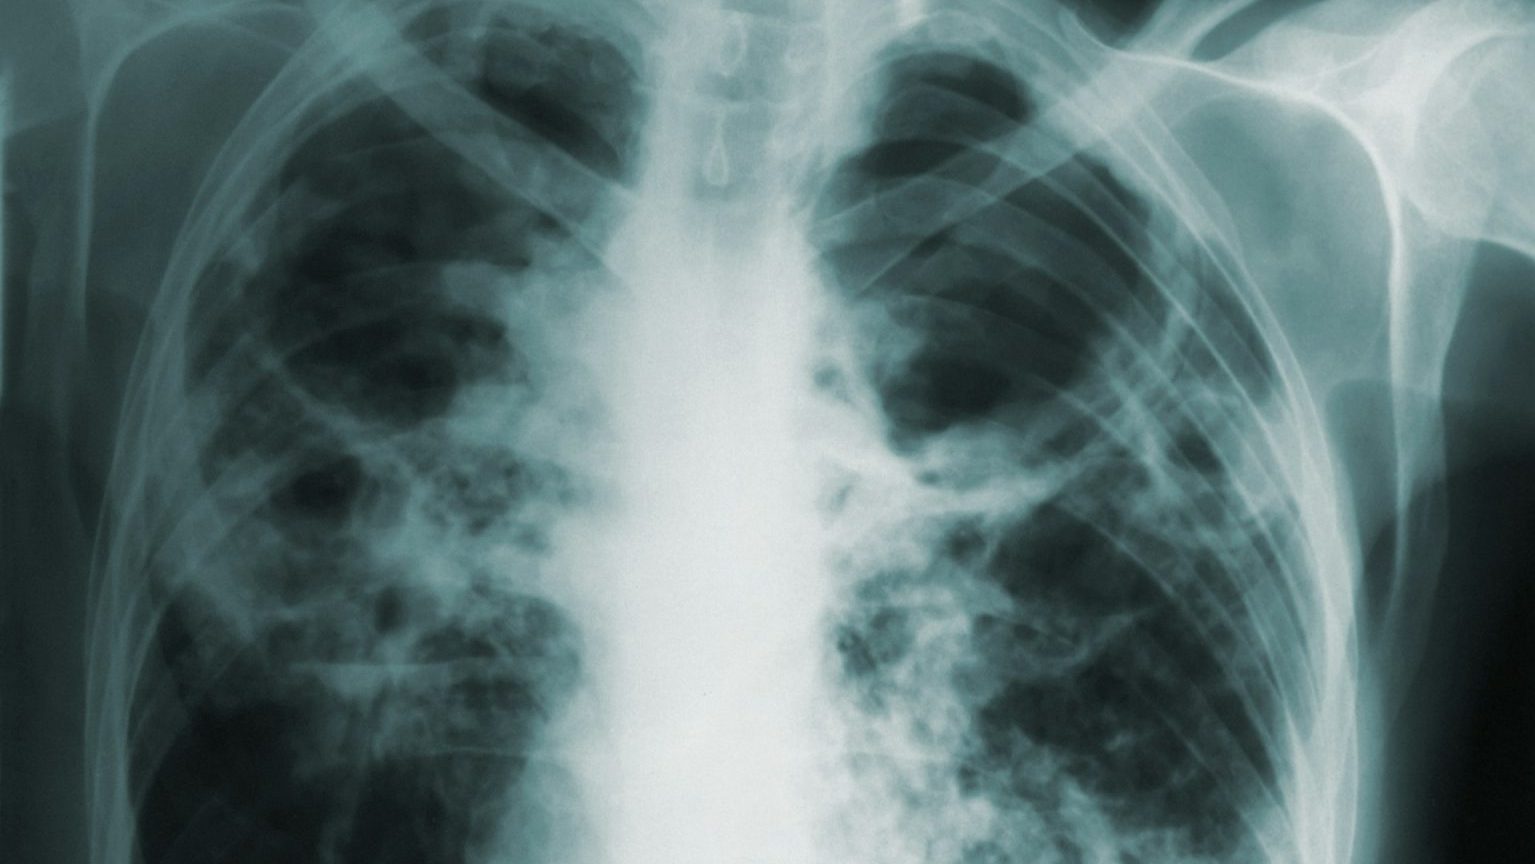

The problem: When blood vessels in the brain become clogged or constricted, they can cut off oxygen and nutrients to the brain and destroy brain cells. This is the root cause of ischemic strokes.

Stroke can be treated if caught early, and there are drugs that can break up the blood clots that cause many strokes.

However, after a stroke, the leftover dead tissue triggers an inflammatory response, where immune cells flood the site of injury to clean up any dead or damaged cells so healing can progress.

But prolonged inflammation can also harm good tissue, which can lead to post stroke dementia.

Brain cells are also packed with cholesterol, which is difficult for immune cells to eliminate. So inflammation caused by a stroke might linger for months, spreading to healthy areas of the brain and killing more brain cells.